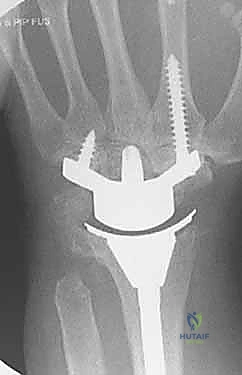

تعتبر عملية زراعة مفصل الرسغ من العمليات الدقيقة التي تتطلب تخطيطاً مسبقاً ومهارة عالية. يقوم الأستاذ الدكتور محمد هطيف بتنفيذ هذه الجراحة وفق أحدث المعايير العالمية المتبعة، وتتضمن الخطوات التالية:

قبل العملية، يتم إجراء صور أشعة سينية (X-rays) وأشعة مقطعية (CT scan) ثلاثية الأبعاد. تساعد هذه الصور الدكتور هطيف في تحديد حجم التلف بدقة، واختيار الحجم والنوع المناسب للمفصل الصناعي (والذي يتكون عادة من أجزاء معدنية من التيتانيوم ومكونات بلاستيكية عالية الكثافة من البولي إيثيلين).

6. تثبيت المفصل الصناعي النهائي

يتكون المفصل الصناعي من جزأين رئيسيين: الجذع الكعبري (الذي يُزرع في عظمة الكعبرة في الساعد) والجذع الرسغي (الذي يُزرع في عظمة المشط الثالثة في اليد). يتم تثبيت هذه الأجزاء إما باستخدام الإسمنت العظمي الطبي، أو عن طريق الانحشار الميكانيكي الدقيق (Press-fit) الذي يسمح بنمو العظم داخل المفصل الصناعي. بين هذين الجزأين المعدنيين، توضع قطعة بلاستيكية عالية الجودة تعمل كغضروف صناعي يسمح بالحركة السلسة.